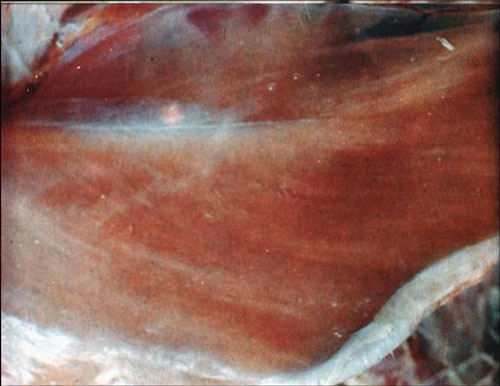

经过剖检后病鸡内脏情况是什么样的?最常见的病变为坐骨神经、臂神经等单侧性肿大变粗,比正常增大2-3倍。内脏器官可能出现一个或多个肿瘤,其中以卵巢最易受害,颜色消退,肿大,表面颗粒状,病变器官可增大数倍,肿瘤切面坚实平滑。皮肤肿瘤多见于腿部、颈部和长有粗大羽毛的部位,形成肿瘤性结节。